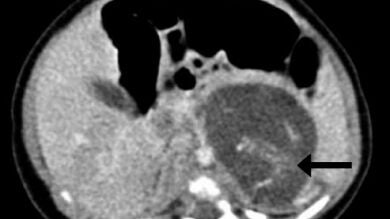

Cada “feto” tenía cuatro extremidades, piel, una caja torácica, los intestinos y un tejido cerebral primitivo. Ambos estaban unidos por un cordón umbilical, según describen los especialistas que atendieron atónitos al parto, que tuvo lugar en 2010.

El estado de desarrollo de los fetos (o tumores) podría situarse entre las ocho y diez semanas de gestación, según los expertos. Tenían espinas dorsales, genitales externos ambiguos y aún no habían desarrollado el cráneo.

La teoría habitual para estos casos es que los fetos adicionales se desarrollan desde el principio del embarazo, para luego ser absorbidos por el principal, dejando de crecer. Pero aquí las dos masas con tejido no se descubrieron hasta las 37 semanas, teniendo las dos un idéntico nivel de desarrollo de órganos.